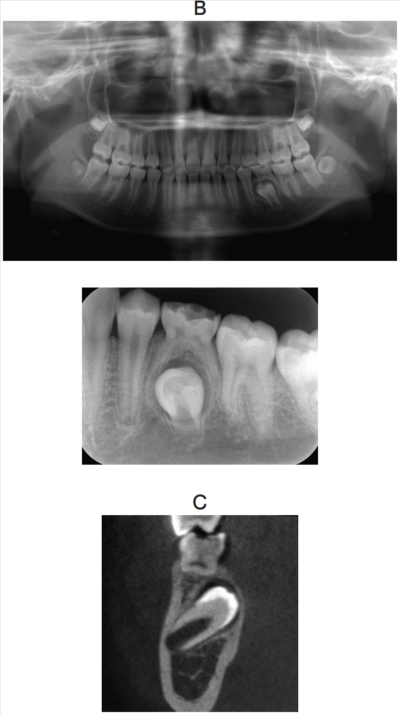

14歳の男子。下顎左側第二乳臼歯が交換しないため精査を希望して来院した。3年前から気付いていたがそのままにしていたという。初診時の口腔内写真、エックス線写真及び歯科用コーンビームCTを別に示す。

⎾Eに対する適切な対応はどれか。1つ選べ。